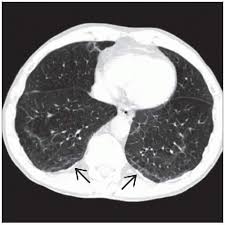

Asbestosis / Asbestos Related Diseases Asbestosis Pleural Plaques - Asbestosis is a process of diffuse interstitial fibrosis of the lung due to exposure to asbestos dust.. Asbestosis refers to later development of diffuse interstitial fibrosis secondary to asbestos fiber inhalation and should not be confused with other asbestos related diseases. Also called diffuse pulmonary fibrosis or pneumoconiosis, asbestosis is the leading cause of death for people exposed to asbestos. Asbestosis is a lung disease that develops when asbestos fibers cause scarring in your lungs. Looking for online definition of asbestosis in the medical dictionary? Though there is no cure, it can be managed with treatment.

Though asbestosis is believed to be mostly an occupational disease, there. Asbestosis is a lung disease that occurs from breathing in asbestos fibers. A plaque caused by asbestos exposure on the diaphragmatic pleura. Asbestosis is a typical pneumoconiosis (interstitial lung disease caused by inhaled inorganic the development and severity of asbestosis is related to the degree and duration of asbestos exposure. What is the treatment for asbestosis? Asbestosis refers to later development of diffuse interstitial fibrosis secondary to asbestos fiber inhalation and should not be confused with other asbestos related diseases. It is caused exclusively by exposure to asbestos, but it is usually not. Though there is no cure, it can be managed with treatment. In most cases patients dont show any symptoms for. Asbestosis is a chronic lung condition that is caused by prolonged exposure to high concentrations of asbestos fibers in the air. Asbestosis is long term inflammation and scarring of the lungs due to asbestos fibers.4 symptoms may include asbestosis. Dangers, testing, symptoms, and cancers what tests diagnose asbestosis? The disease can get worse over time.

We also discuss treatments and tests to diagnose asbestosis. Though asbestosis is believed to be mostly an occupational disease, there. Asbestos exposure may also increase the risk of asbestosis (an inflammatory condition affecting the lungs that can cause shortness of breath, coughing, and permanent lung damage). Though there is no cure, it can be managed with treatment. A plaque caused by asbestos exposure on the diaphragmatic pleura. Asbestosis is a type of pneumoconiosis caused by the inhalation of asbestos fibers and occurs primarily as a result of occupational exposure. Asbestosis is a respiratory disease caused by inhaling asbestos fibers. Asbestosis is a lung disease that develops when asbestos fibers cause scarring in your lungs. Asbestosis is a process of diffuse interstitial fibrosis of the lung due to exposure to asbestos dust. Prolonged exposure to these fibers can cause lung tissue scarring and shortness of breath. Asbestosis is long term inflammation and scarring of the lungs due to asbestos fibers.4 symptoms may include asbestosis. Asbestosis is a typical pneumoconiosis (interstitial lung disease caused by inhaled inorganic the development and severity of asbestosis is related to the degree and duration of asbestos exposure. Asbestosis refers to later development of diffuse interstitial fibrosis secondary to asbestos fiber inhalation and should not be confused with other asbestos related diseases.